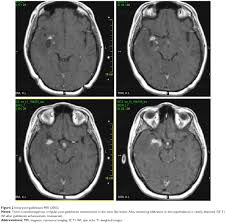

Primary Whipple Disease Of The Brain Case Report With Long Term Clini Ndt

Mr Imaging Of Central Nervous System Whipple Disease A 15 Year Review American Journal Of Neuroradiology

Cerebral Whipple S Disease Laboratory Data And Mri Findings Download Table

Diagnosis And Management Of Whipple S Disease Of The Brain Practical Neurology